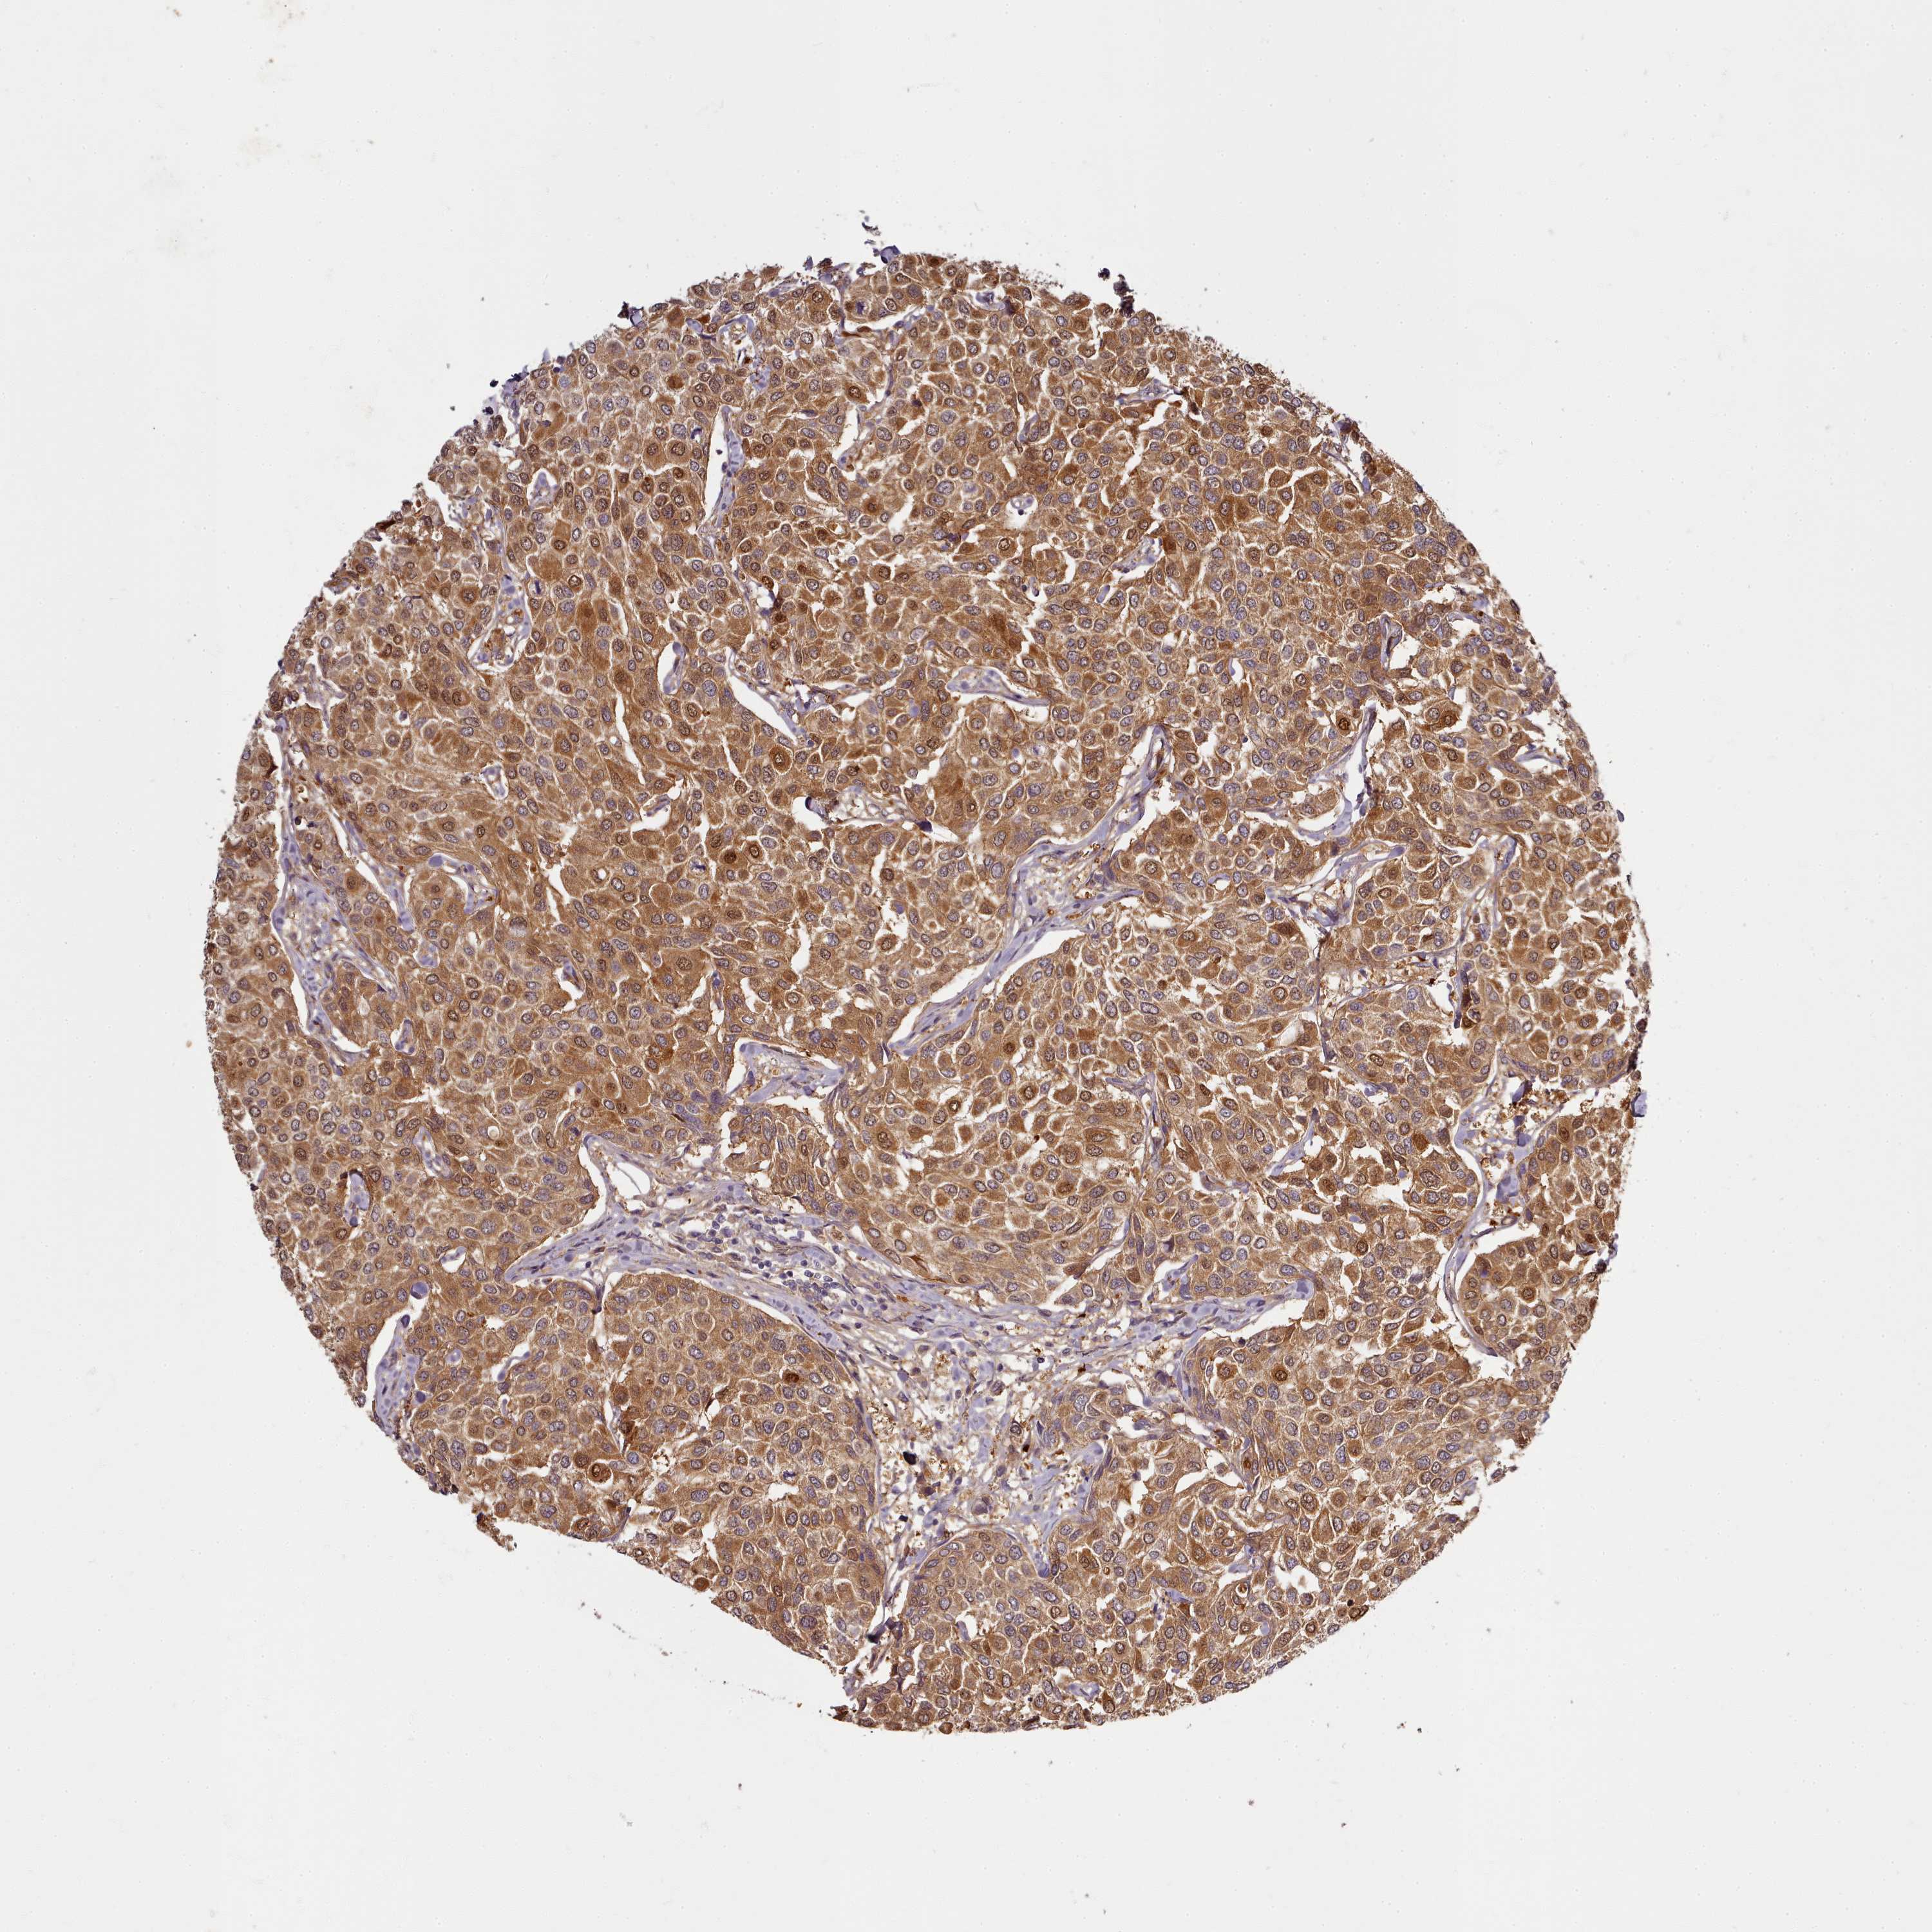

CANCER BREAST CANCER Show tissue menu

BRCA TCGA BRCA VALIDATION PROTEIN EXPRESSION

Breast cancer

Human cancer

Breast invasive carcinoma